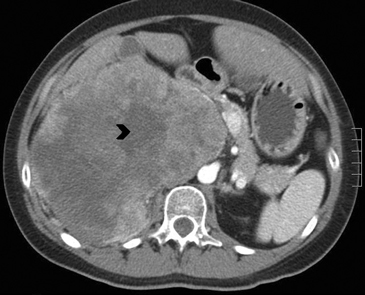

En TC sin contraste por lo general se observa una masa heterogénea, especialmente en caso de lesiones de mayor tamaño por la presencia de necrosis. Entre un 19 a 33% de los casos se identifican calcificaciones. Luego de la administración de contraste su refuerzo es heterogéneo y su patrón de lavado es consistente con una enfermedad maligna (Figura 22).

Los sitios más habituales de metástasis son hígado, pulmón, además de la invasión de las estructuras vasculares adyacentes, especialmente de la vena cava inferior, hallazgo que constituye una consideración fundamental al momento de planificar el abordaje quirúrgico (Figura 23 a y b).

Figura 23. Carcinoma suprarrenal derecho. Corte axial de resonancia magnética ponderado en T2 con saturación grasa (a) en que se demuestra una masa suprarrenal derecha con áreas hiperintensas en su espesor probablemente determinadas por necrosis (flecha) y corte coronal en secuencia TRUFISP (b) en que se observa un trombo tumoral que expande el lumen de la vena cava inferior (cabeza de flecha).Puede también presentar invasión directa de otras estructuras vecinas, como riñón, páncreas, bazo y diafragma.

En RM15 estas lesiones presentan intensidad de señal variable tanto en secuencias ponderadas en T1 como T2, dependiendo de la presencia de componentes necróticos y hemorrágicos, que como ya se mencionó es un hallazgo frecuente. Las áreas de necrosis suelen aparecer hipointensas en T1 e hiperintensas en T2, y las áreas de hemorragia si es en fase subaguda, vale decir aproximadamente una a siete semanas, se observara hiperintensidad de la lesión tanto en secuencia T1 y T2. En fase crónica (a partir de las 7 semanas en adelante) producto del deposito de hemosiderina y la presencia de una capsula fibrosa, las imágenes demuestran un anillo hipointenso tanto en secuencias T1 como T2. Con la administración de gadolinio ev se observa refuerzo de las porciones viables de tumor, con lo que se intensifica la señal.